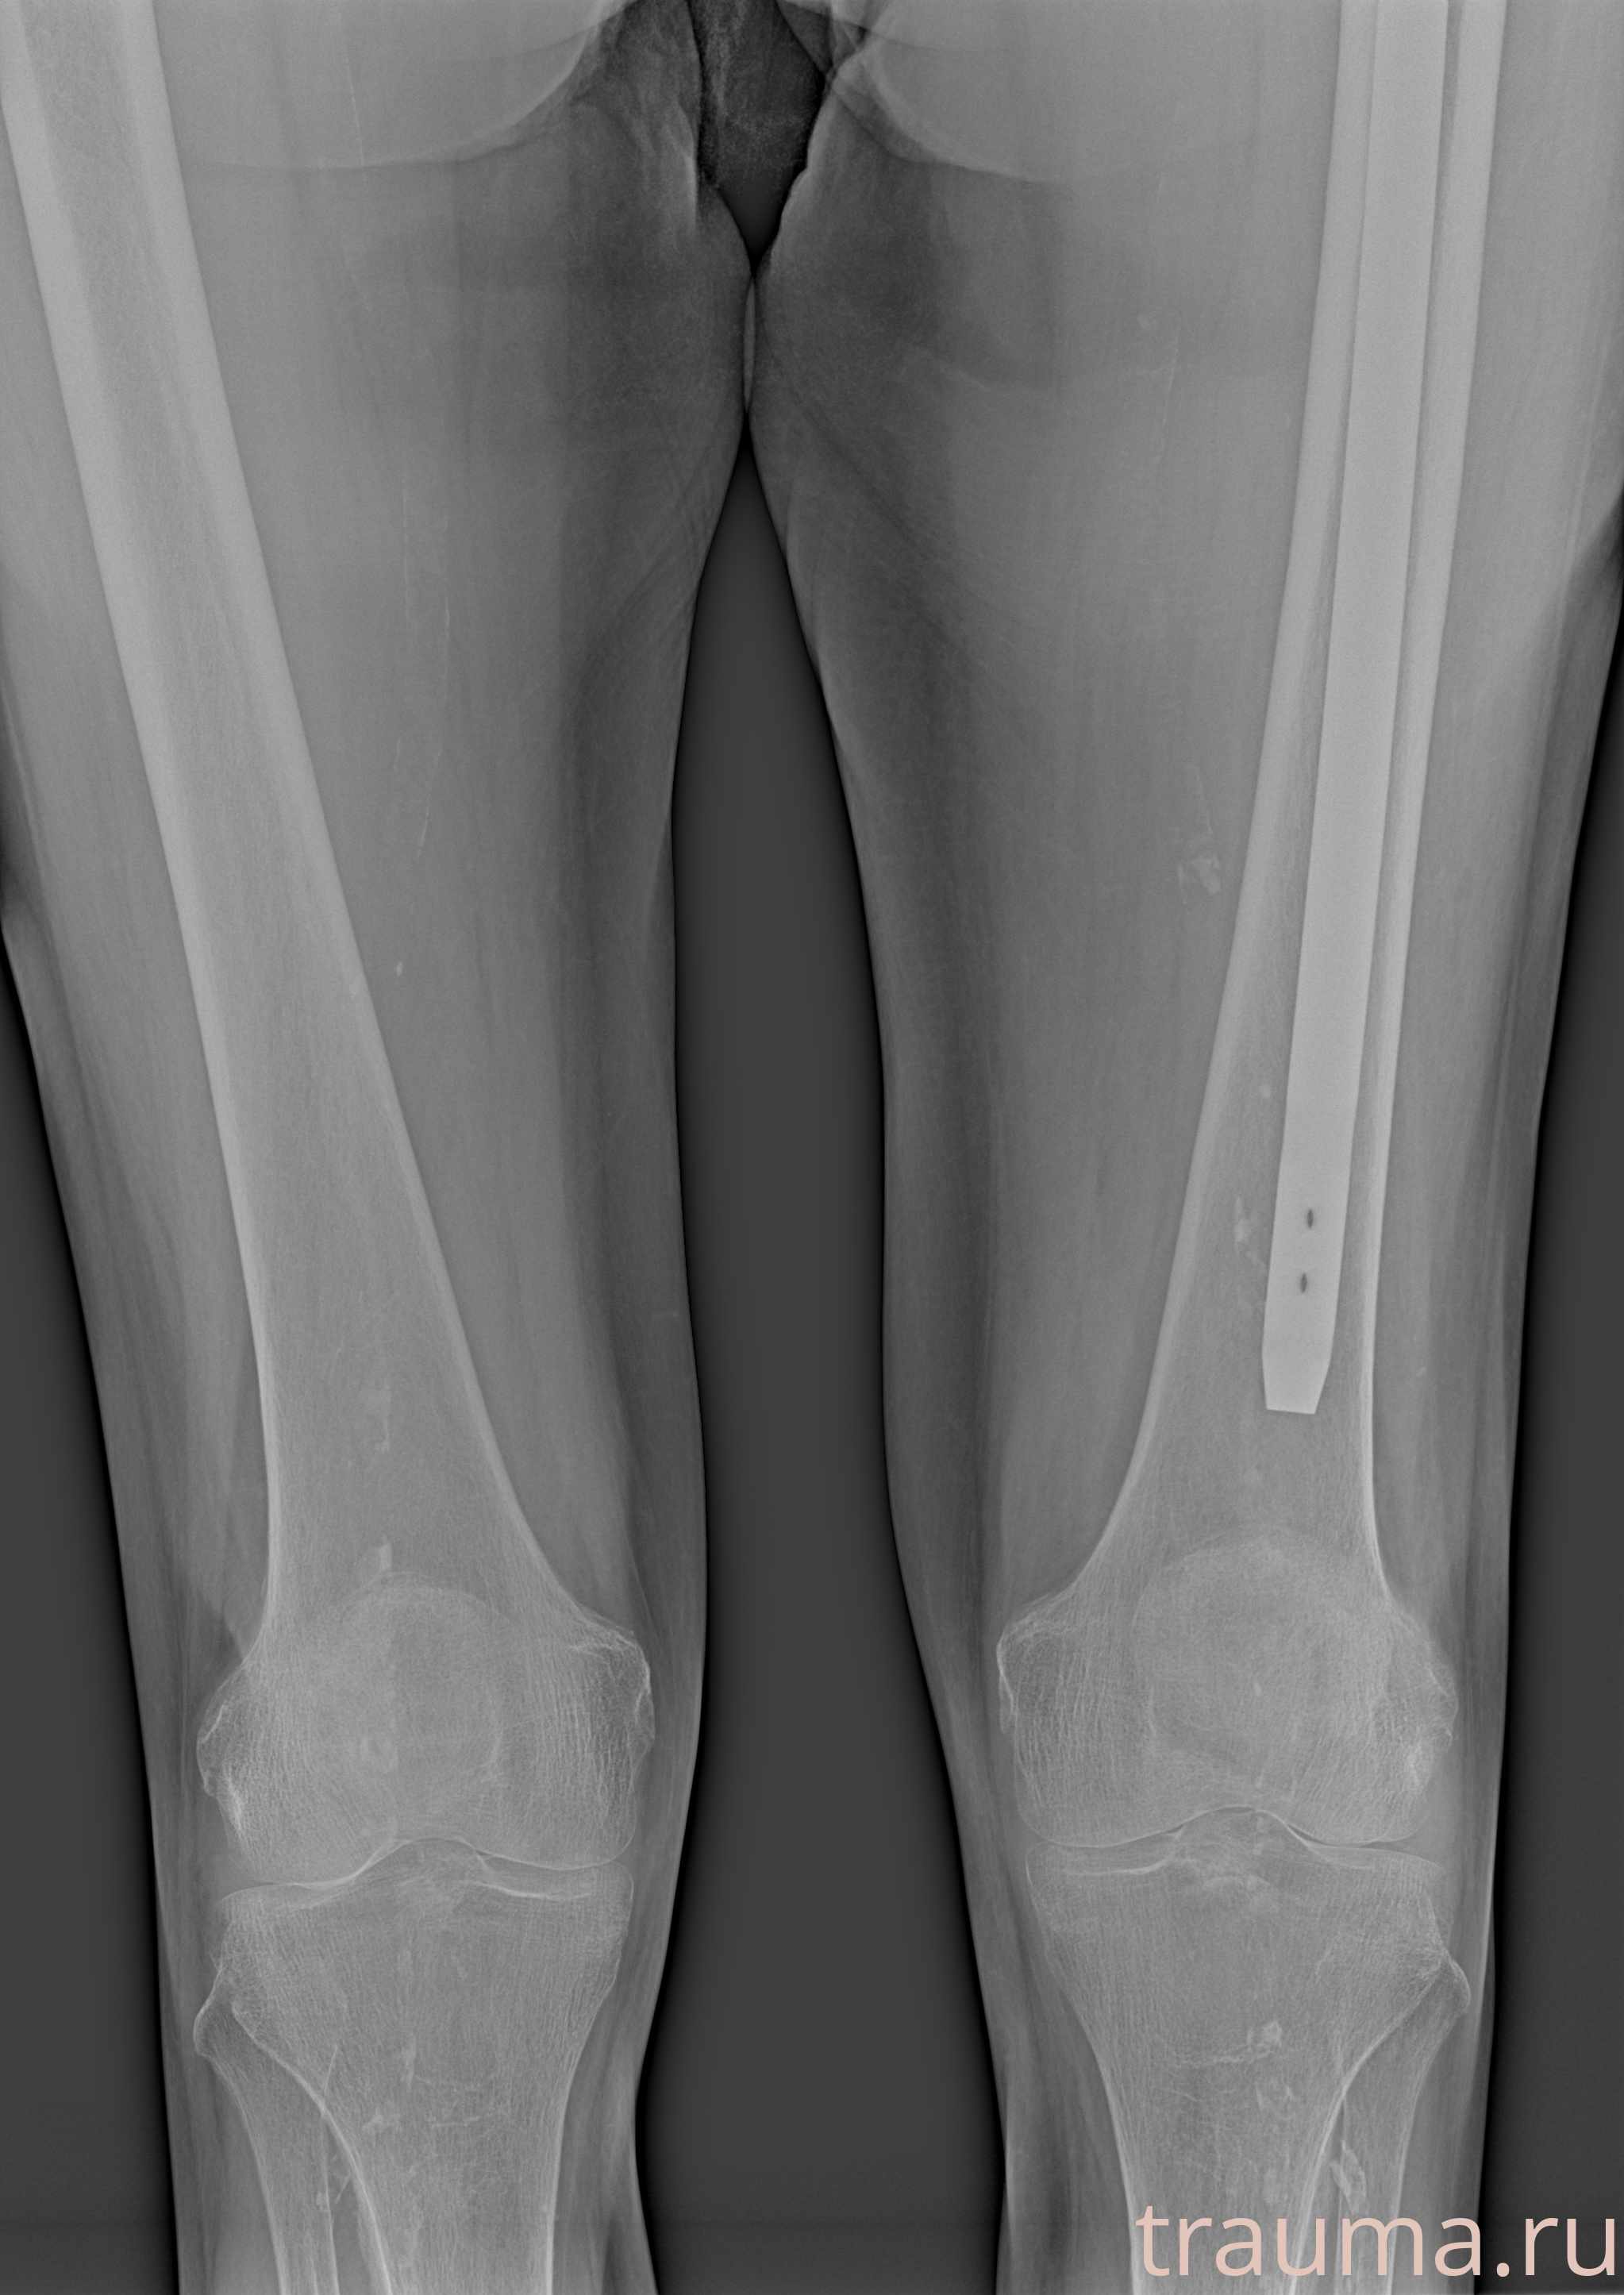

Рентгенограммы

Рентген на дому: по вашему адресу приезжает врач-рентгенолог, травматолог-ортопед с мобильным рентгеновским аппаратом, проводит диагностику травмы или заболевания, делает необходимые рентгенограммы, дает рекомендации по дальнейшему лечению. Получить качественные снимки в домашних условиях возможно благодаря уникальной методике, разработанной МосРентген Центром для института  Склифосовского